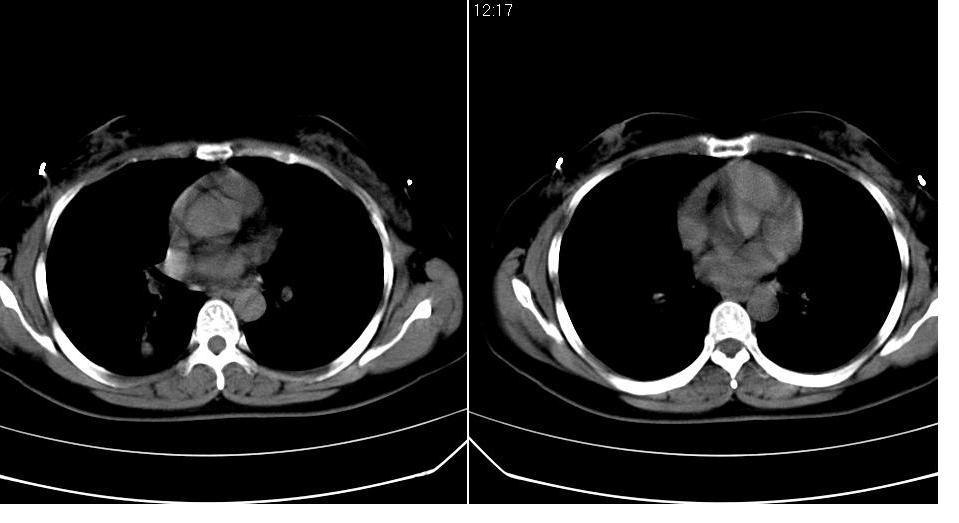

女 40岁,胸片体检发现右肺肿块,无任何症状。

考虑侵润性结核

肺动静脉瘘可考虑,建议增强

典型结核表现